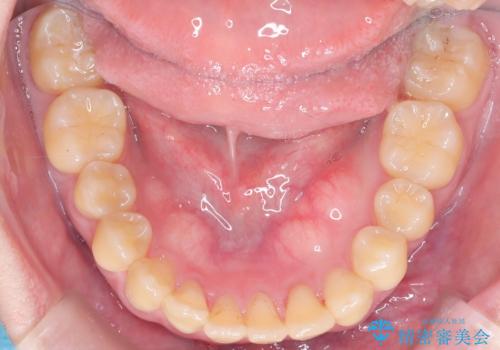

前歯の開咬とシザーズバイトを改善|インビザライン矯正

- 治療計画

前歯が噛まないため咀嚼が困難で、シザーズバイトにより噛み合わせに不調を感じていました。インビザラインを用いて、透明なマウスピースによる目立ちにくい矯正治療を実施。奥歯のシザーズバイトを改善した後、前歯の歯列を緻密に調整し、噛み合わせを整えました。定期的なマウスピース交換を通じて徐々に歯列が改善され、治療終了後には前歯が正常に咬合するようになり、噛み合わせの機能性と審美性が共に向上しました。